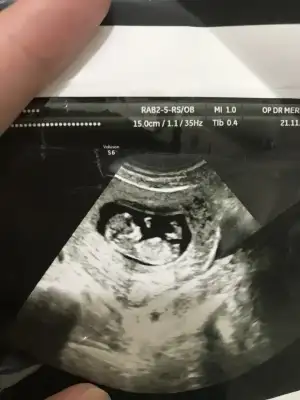

bebegime kız demiştiniz ve doğru çıktıminnoş kızım olacak çok şükür

12 haftalık usg